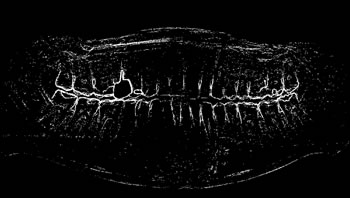

Image annotation

The process of annotating the images of our proposed data set occurred in two parts. First, it was initiated by the upper jaw through the annotation of the third right upper molar and making the annotation of all the teeth of the upper arch to the third left upper molar. Then, the same process was performed on the lower jaw with all the teeth, and in the same direction as the upper jaw, from left to right, starting with the annotation of the third right lower molar, and annotating all teeth from the lower arch to the lower third molar. Figure 4 illustrates the tooth annotation process through a panoramic X-ray image of the data set.